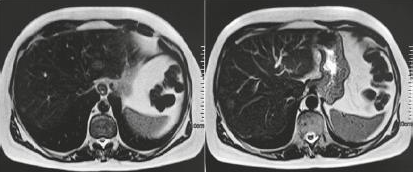

caso de tumor neuroendócrino metastático de intestino delgado com quadro característico de síndrome carcinoide. Fonte: https://doi.org/10.1590/0102-672020190001e1492

Fonte: https://doi.org/10.1590/S0100-39842007000300004